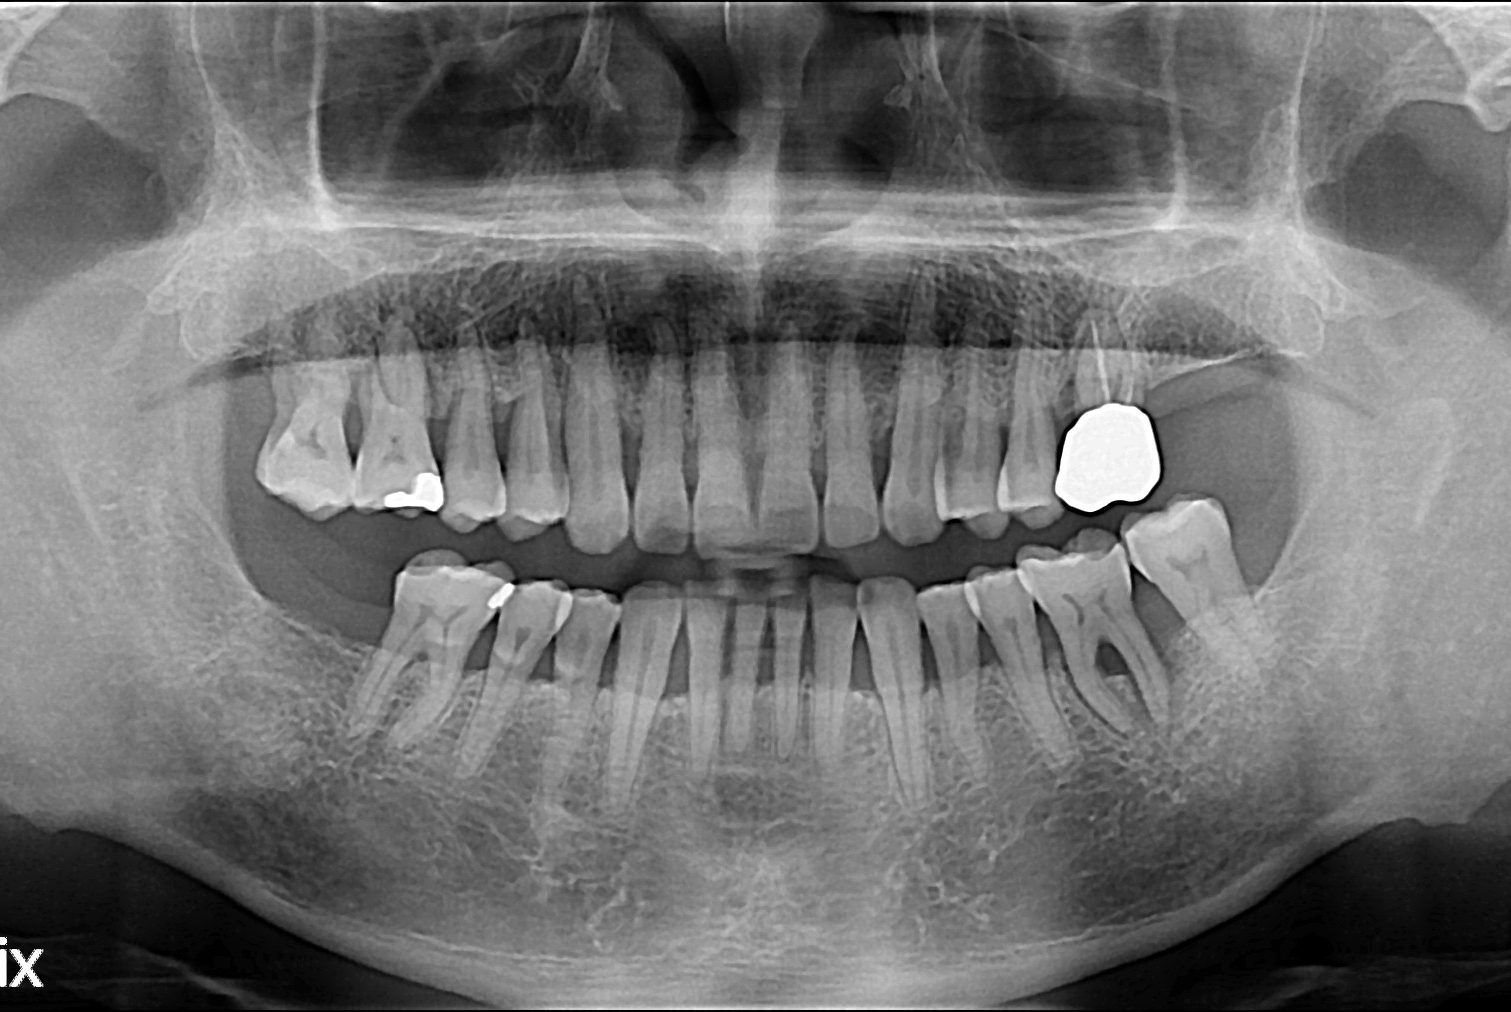

[임플란트] 임플란트

치료후 : 2018-11-01

세종치과는 많은 환자와 다양한 케이스를 바탕으로 항상 편안한 임플란트 수술을 제공하고자 노력하고,

오래동안 튼튼히 쓸 수 있는 임플란트 수술을 가장 큰 목표로 삼고 있습니다